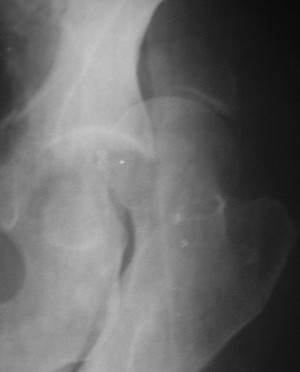

Послеоперационный снимок прямой 5/05/03

Больной 18 мая 2003 года в автоаварии получил перелом левой вертлужной впадины, вывих бедра. Госпитализирован в один из стационаров области.Вывих вправлен. В последствии бедро вывихивалось еще дважды. На консультацию был представлен снимок от 19.05.03г., больной переведен к нам 3.06.03г. Снимок при поступлении - перелом впадины, задне-верхний вывих бедра. 05.06.2003 г. выполнено открытое вправление вывиха левого бедра и остеосинтез стенки вертлужной впадины двумя винтами. Послеоперационный период без осложнений. Объем движений в левом тазобедренном суставе восстановился полностью. Выписан на амбулаторное лечение в удовлетворительном состоянии с рекомендациями 3 месяца ходить на костылях без нагрузки на оперированную конечность. На контрольных рентгенограммах левого тазобедренного сустава 13.10.2003 г. - признаки консолидации перелома; плотность, форма головки и состояние суставных поверхностей удовлетворительные. Разрешена дозированная осевая нагрузка, на конечность с использованием дополнительной опоры. 19.12.2003 г. больной обратился с жалобами на боли в левом тазобедренном суставе. На рентгенограммах левого тазобедренного сустава 19.12.2003 г., 20.02.04г. - асептичекий некроз головки бедра. 5.04.04г. - эндопротез. Сейчас ходит без трости, не хромает. Особенность эндопротезирования - при удалении винтов прослежена линия перелома заднего края впадины и предложено установить чашку несколько меньшего диаметра, чтобы она была покрыта несломанной частью.